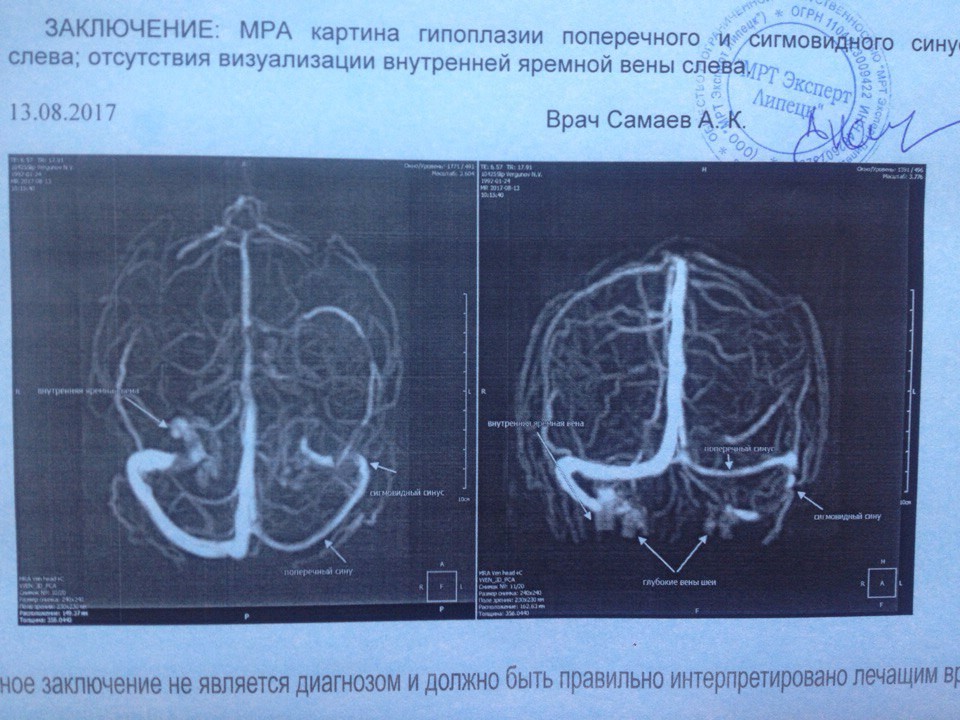

Особенности и диагностика левостороннего кровотока

.jpg)

Раздел: Моменты озарения